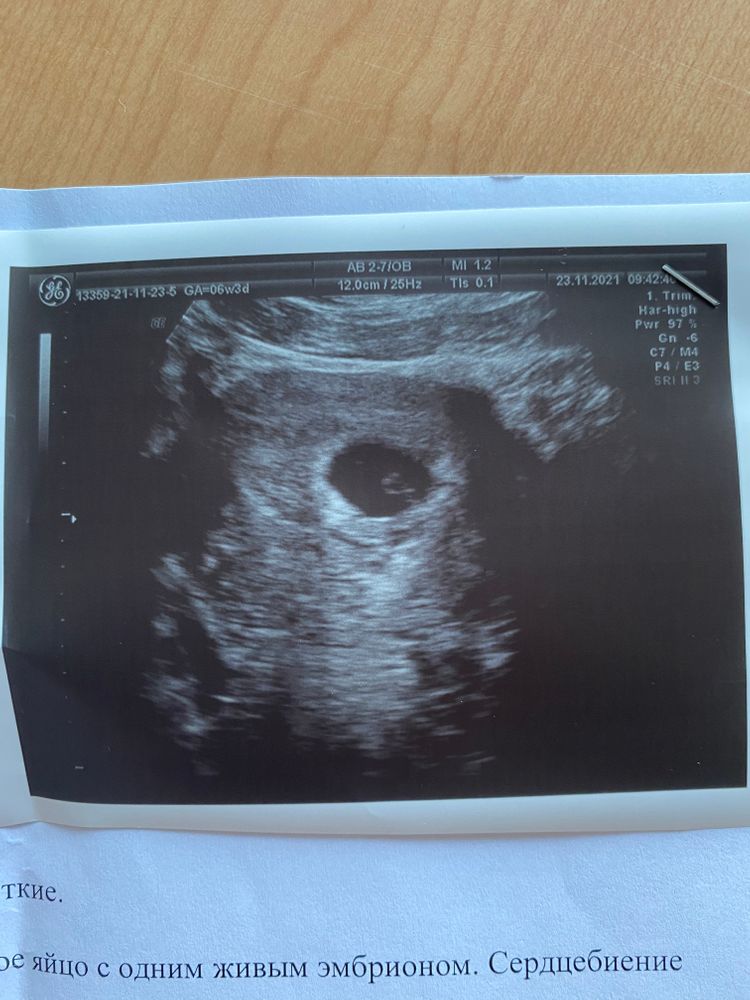

Наконец-то сходила на узи в 6,3-по узи ставят ровно 6 неделек, сердцебиение 126 уд/мин , немного успокоилась ) Три дня назад у меня начал проявляться токсикоз , безумно мутит от всех запахов, из еды хочется ТОЛЬКО вредного! Поставила себе цель набрать за Б не больше 10 кг и уже +2 ((( Заинтересовалась методом Рамзи по определению пола, но так особо и не поняла ) Девочки, может кто-нибудь разбирается , фото приложу , смотрели по животу